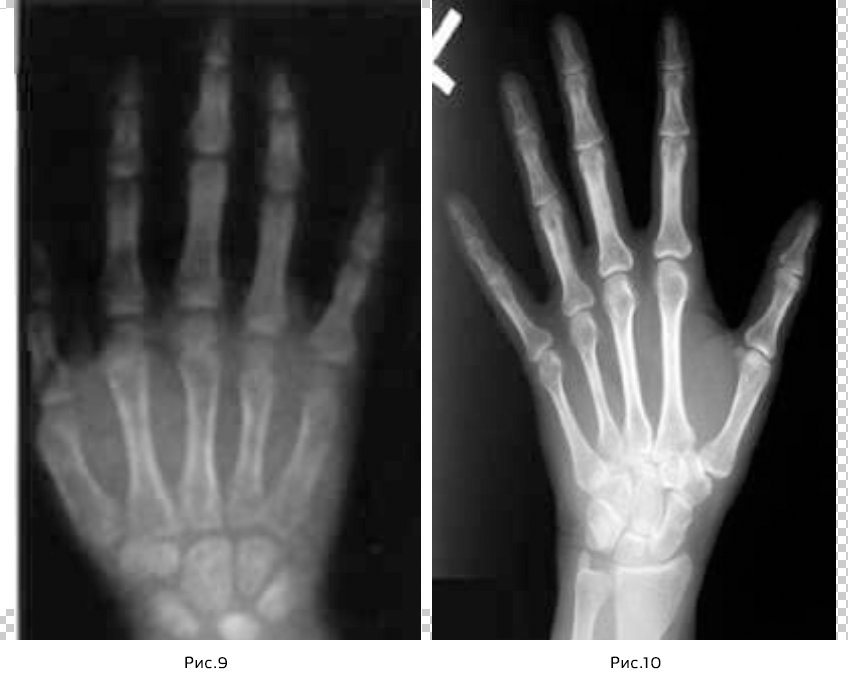

Еще одним методом оценки степени роста является рентгенограмм кисти. Для анализа скелетной зрелости приблизительно до 9 года жизни используется степень минерализации костей запястья, развитие пястной кости и фаланг.

Оценка заключается в определении соотношений величин эпифиза (расширенный конец трубчатой кости) (Рис.4) к диафизу (центрального отдела трубчатой кости). (Рис.5)

Равная ширина диафиза и эпифиза обозначается как «=» (Рис.6) , охватывание диафиза эпифизом в виде колпачка – «cap»(Рис.7) , при полном окостенении – «unit(u)» или также «closed (с)». (Рис.8)